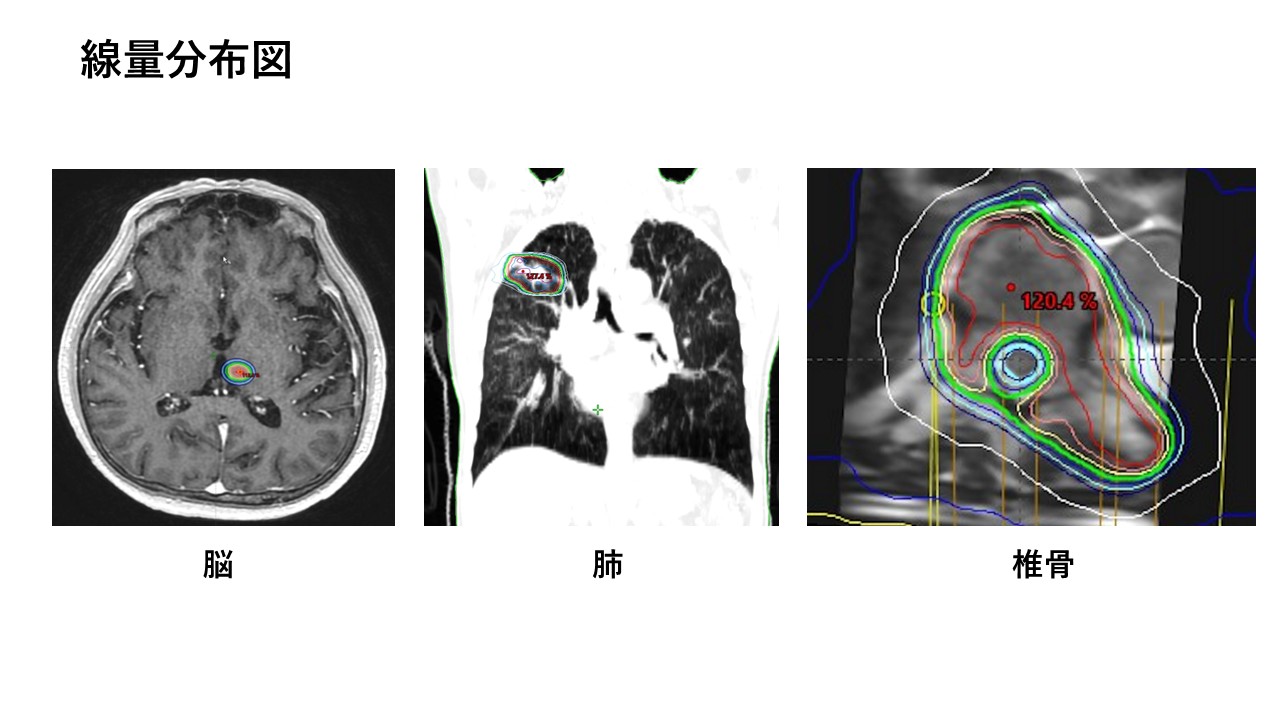

3. 定位放射線治療(Stereotactic radiotherapy: SRT)

比較的小さながん病巣に対し、周囲の正常臓器を避けて高線量の放射線を集中的にピンポイントで照射する治療です。ミリ単位の正確さでがん病変への強力な照射を行います。少ない回数(短期間)で安全に効果的な高線量を投与できます。

脳転移や、早期の肺癌や肝細胞癌などの体幹部の病巣に対して適用します(体幹部定位放射線治療:Stereotactic body radiotherapy: SBRT)。椎骨(背骨、腰骨)の骨転移には脊髄(神経)をくり抜くように避けての照射が可能です。